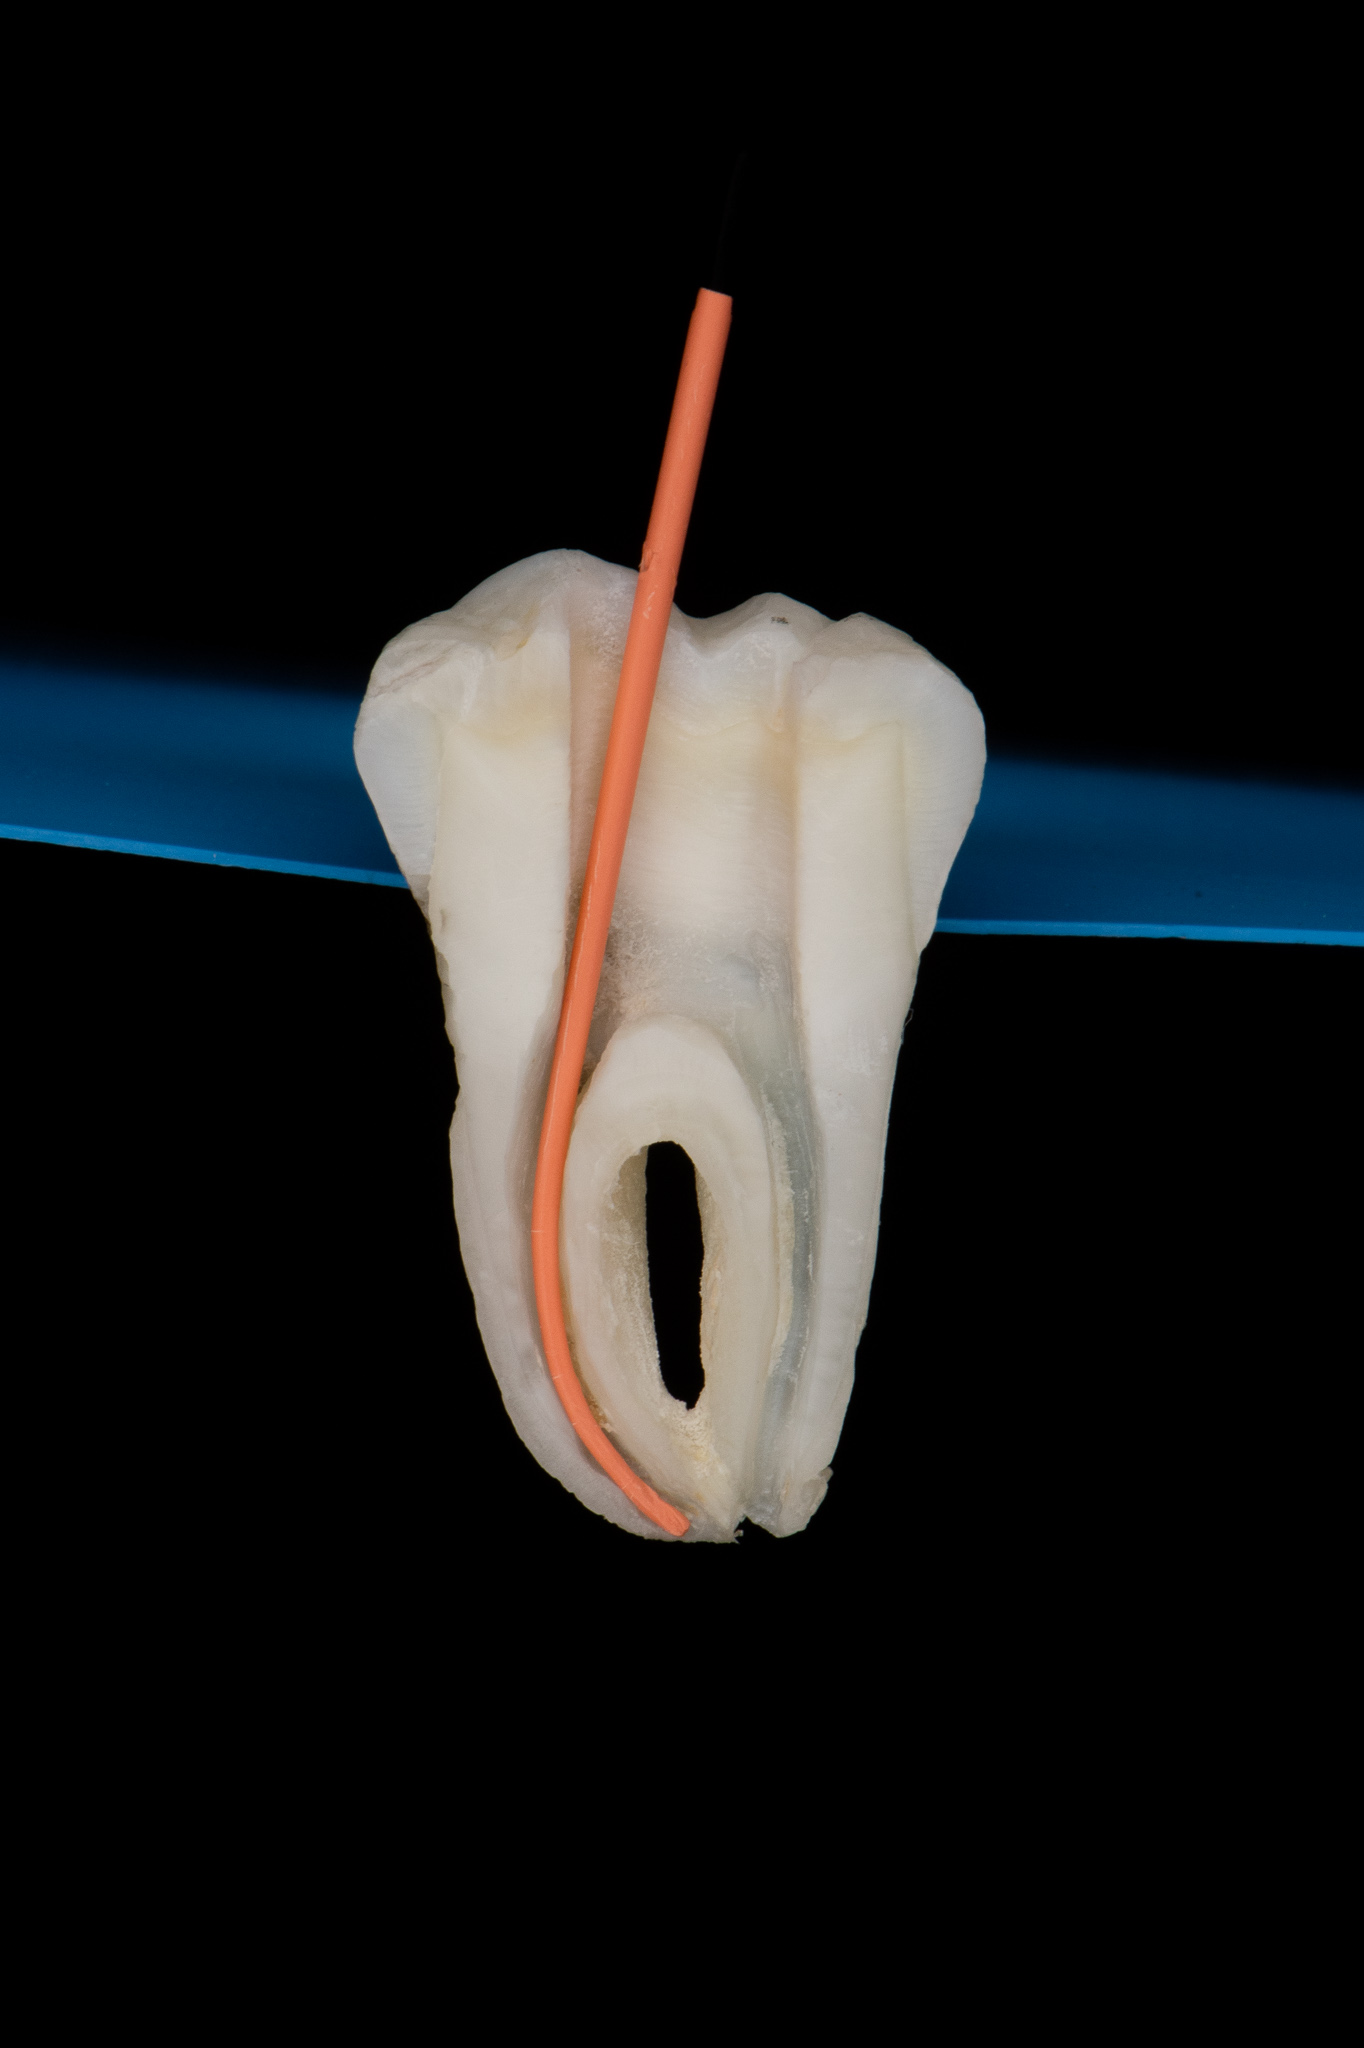

Endodoncja czyli leczenie kanałowe pozwala, na wiele lat, utrzymać w zdrowiu zęby martwe, które w przeciwnym razie wymagałby usunięcia. W naszym gabinecie prowadzimy leczenie kanałowe pierwotne jak również powtórne (ReEndo) z wykorzystaniem nowoczesnych technik i narzędzi takich jak mikroskop zabiegowy, rotacyjne systemy udrażniania kanałów czy wypełnienie płyną falą gutaperki.

Pacjent zgłosił się do gabinetu w celu zaopatrzenia złamanego zęba (kła) w koronę protetyczną. W badaniu radiologicznym widoczna jest resorpcja materiału wypełniającego kanał po dawnym leczeniu endodontycznym oraz tworząca się zmiana zapalna w okolicy wierzchołka korzenia; z uwagi na konieczność wykorzystania zęba jako filar protetyczny przeprowadzono powtórne leczenie kanałowe (ReEndo) z wykorzystaniem nowoczesnych narzędzi rotacyjnych oraz mikroskopu zabiegowego. Kanał wypełniono szczelnie techniką obturacji płynną falą gutaperki (wypełnienie na ciepło).

Ząb posłużył do stabilnej odbudowy protetycznej.